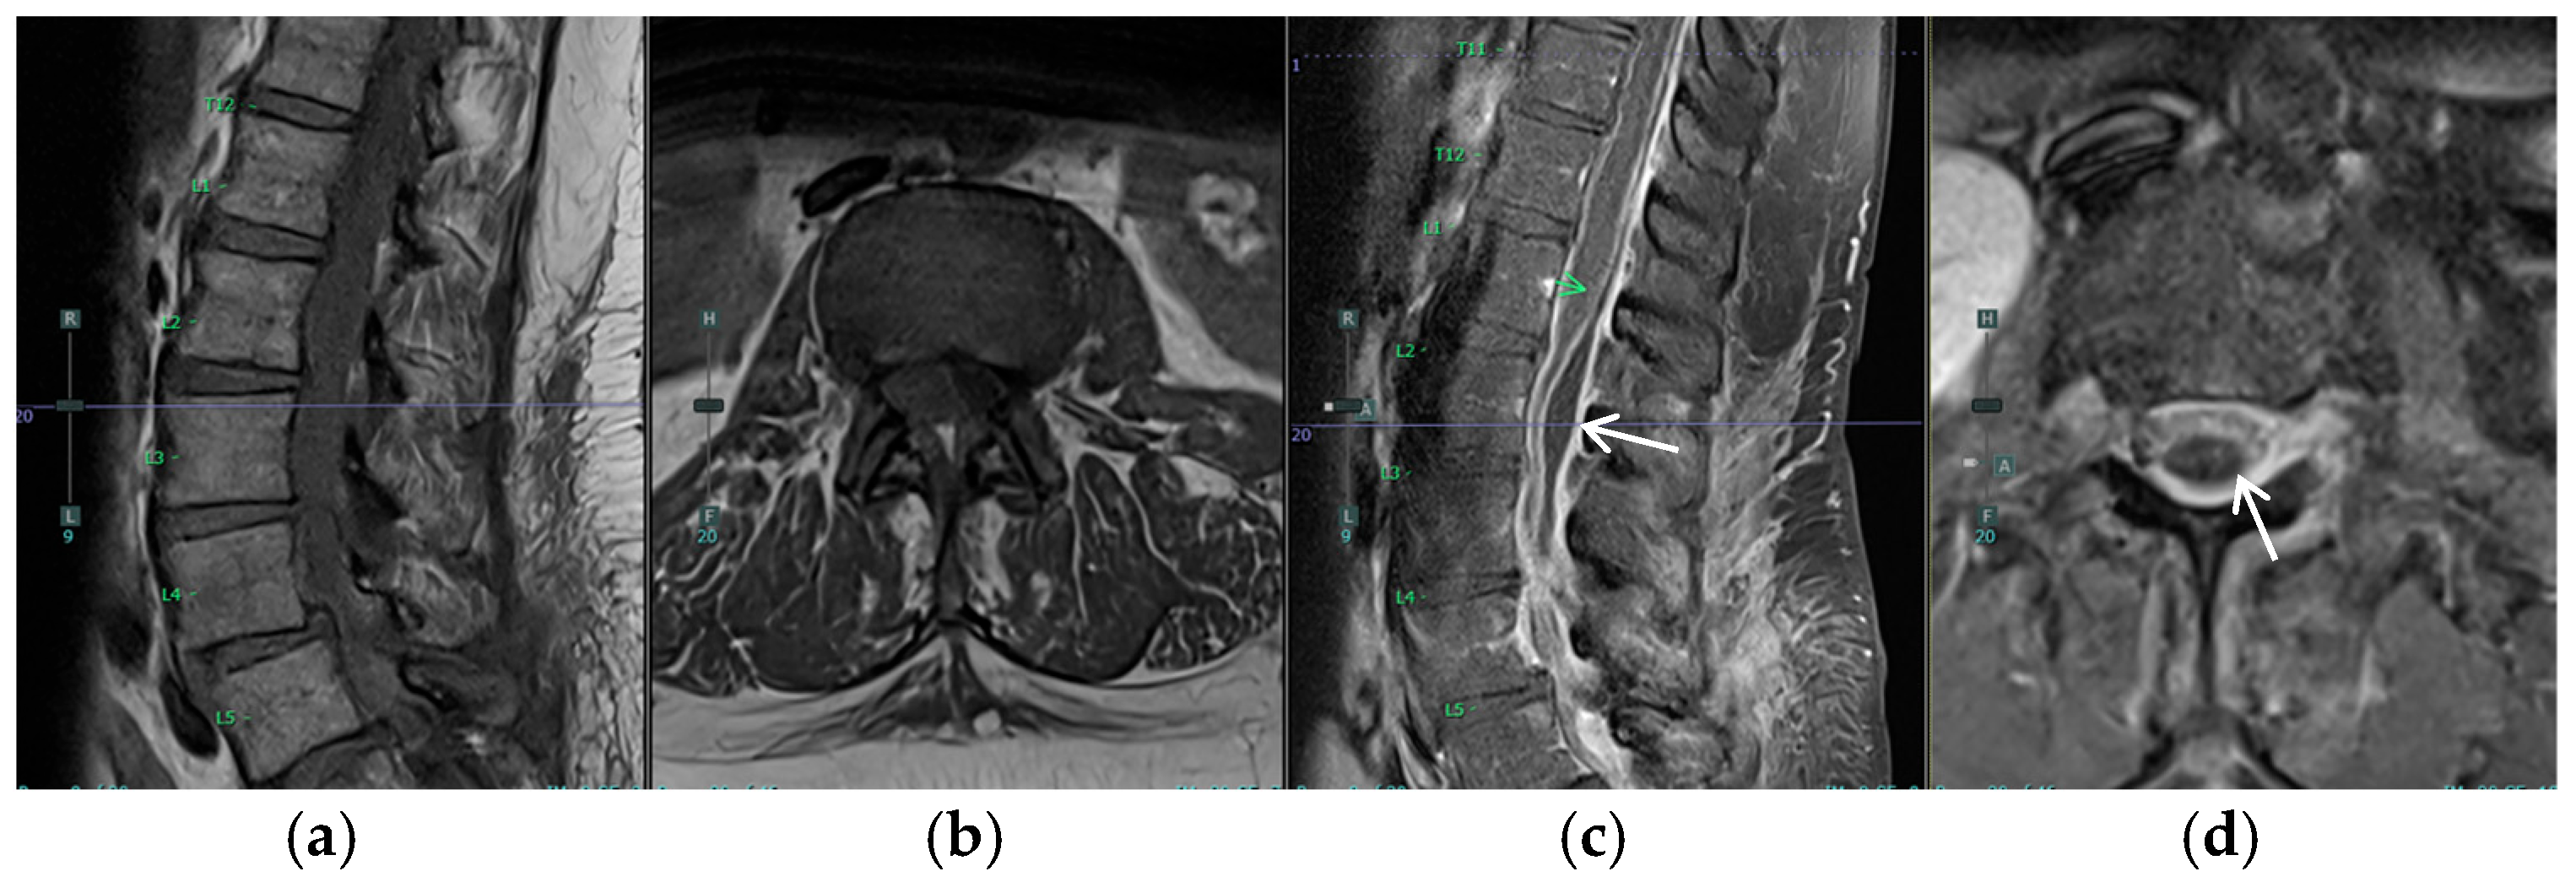

The patient’s postoperative course was notable for the development of urinary retention and persistent back pain on postoperative day 2 (POD2). By POD3, she had developed new bilateral posterior leg pain with ambulation, in contrast to her preoperative unilateral left-sided symptoms. MRI on POD4 revealed an unexpected finding: a new peripherally enhancing dorsal subdural collection at the L2 level, significantly higher than the L5/S1 surgical site, resulting in moderate to severe thecal sac narrowing and compression of the cauda equina nerve roots (Figure 3 and Figure 4). The differential diagnosis for the intradural collection included several possibilities: migrated hydrogel sealant, epidural abscess, seroma, or acute hematoma. The imaging characteristics, particularly the peripheral enhancement pattern and the temporal relationship to sealant placement, along with the patient’s clinical course, were most consistent with migrated hydrogel sealant. Conservative management with close observation of symptom progression chosen given the patient’s stable neurological status and the known property of PEG-based hydrogels to degrade over time. The patient’s urinary retention resolved by POD6. Her bilateral leg pain showed improvement regarding POD9. Her symptom improvement further supported the diagnosis of migrated hydrogel sealant. She was discharged home with a six-week course of intravenous antibiotics.

Figure 3. Postoperative MRI of the lumbar spine. The white arrows identify the new postoperative dorsal subdural collection, resulting in thecal sac narrowing and compression of the cauda equina nerve roots. (a) Sagittal T1, (b) Axial T1 at L3, (c) Sagittal T1 with contrast, green arrow: new peripherally enhancing dorsal subdural collection at the L2 level, and (d) Axial T1 with contrast at L3.